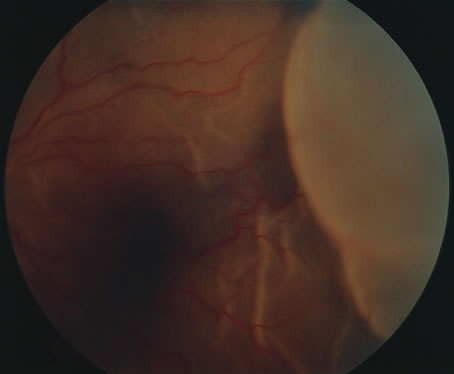

Corneal complications occur in the majority of patients with herpes zoster ophthalmicus. A punctate epithelial keratopathy with pseudodendrite formation is the earliest and most common lesion that occurs. Stromal infiltrates, disciform reactions, and rarely interstitial keratitis are also observed. Scarring and contracture of the lid margin often results in trichiasis, distichiasis, entropion, or ectropion. Corneal sensation is reduced, and neurotrophic ulceration, corneal melting, or perforation may ensue. Extraocular muscle involvement with facial paresis has been observed.11 The acute retinal necrosis (ARN) syndrome is most often caused by the herpes zoster virus, although occasionally it may be a result of herpes simplex infection.12 It is typically described in healthy patients although association with immunosuppressed patients has also been described. Granular, nonhemorrhagic areas of retinal necrosis may be observed in the fundus, often rapidly coalescing with resulting blindness often caused by retinal detachment. There is often an associated vasculitis and vitritis. In immunocompromised patients VZV or HSV retinitis may also take the pattern of progressive outer retinal necrosis (PORN) (Fig. 6). PORN differs from ARN in that the former is multifocal, localized to the outer retina, and is less often associated with vasculitis and vitritis.